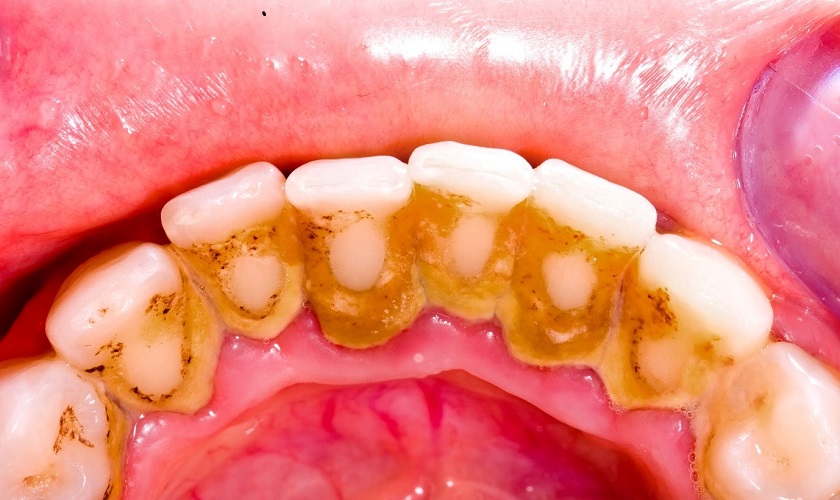

Hình ảnh vôi răng

Cạo vôi răng (hay còn gọi là lấy cao răng) là kỹ thuật nha khoa sử dụng máy siêu âm chuyên dụng để loại bỏ các mảng vôi bám cứng trên răng và dưới nướu. Khác với vệ sinh thông thường, vôi răng là cặn khoáng cứng hình thành từ mảng bám và vi khuẩn, không thể làm sạch bằng bàn chải.

Cạo vôi răng (hay còn gọi là lấy cao răng) là kỹ thuật nha khoa sử dụng máy siêu âm chuyên dụng để loại bỏ các mảng vôi bám cứng trên răng và dưới nướu.

Khác với vệ sinh thông thường, vôi răng là cặn khoáng cứng hình thành từ mảng bám và vi khuẩn, không thể làm sạch bằng bàn chải.